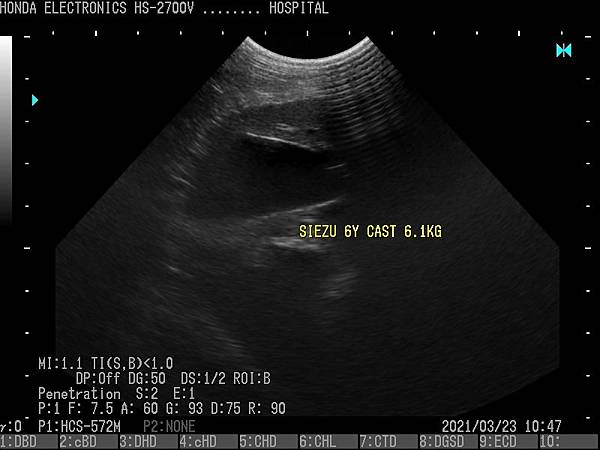

- 通過H-res獲得清晰豐富的單色圖像

HONDA獨創的圖像增強技術 H-res(我們的分辨率技術)

多年來超聲波技術的發展,結晶為“ H-res”圖像增強技術。

可以通過針對每種應用和探頭調整“ H-res”參數來獲得最佳圖像。